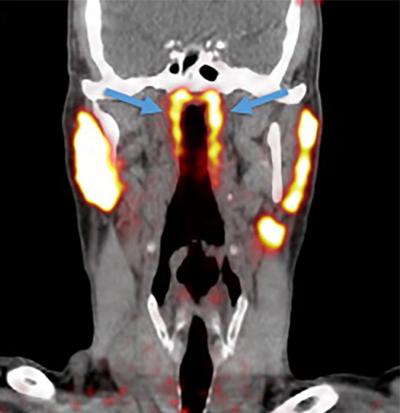

Researchers at the Netherlands Cancer Institute have identified a set of salivary glands deep in the upper part of the throat and have named them “tubarial salivary glands”.

The newly discovered glands are about 1.5 inches (3.9 centimeters) in length on average and are located over a piece of cartilage called the torus tubarius, Livescience reported. According to the researchers, the glands probably lubricate and moisten the upper throat behind the nose and mouth.

The new organ was discovered while scientists were studying prostate cancer cells using PSMA PET-CT technology — a combination of CT scans and positron emission tomography (PET) — which is good in detecting salivary gland tissues. In this technique, a radioactive “tracer” is injected into the patient that binds to the protein PSMA, which is elevated in prostate cancer cells.